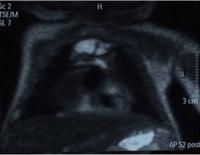

Magnetic resonance imaging (MRI) can be used to differentiate between a hemothorax and other forms of pleural effusion, and can suggest how long the hemothorax has been present for. Fresh blood can be seen as a fluid with low T1 but high T2 signals, while blood that has been present for more than a few hours displays both low T1 and T2 signals.[27] MRI is used infrequently in the trauma setting due to the prolonged time required to perform an MRI, and the deterioration in image quality that occurs with motion.[22]